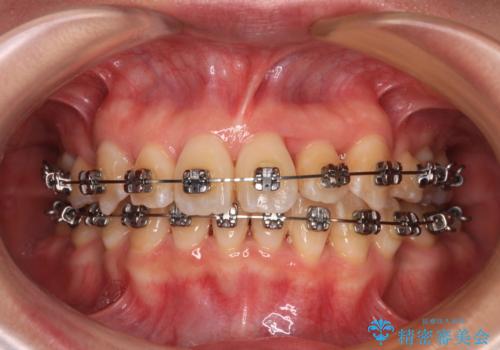

- 矯正装置

- メタルブラケット

- 前歯1本が後ろ側に隠れてしまうほどのデコボコを気にして来院された患者様です。

前歯のデコボコが顕著なのはもちろんですが、左右ともに奥歯の咬み合わせに問題があり、上顎臼歯が前方位にある状態でした。

上顎は左右の第一小臼歯2本を、下顎は左右第二小臼歯2本を抜歯することで、奥歯の咬み合わせを改善しながら、デコボコを解消していくこととしました。